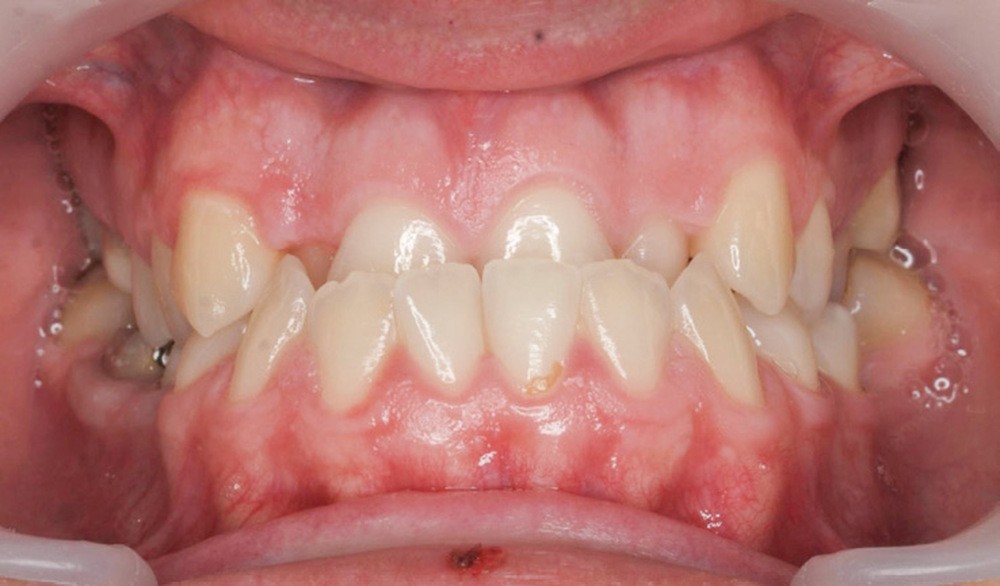

Le traitement vise à améliorer les rapports squelettiques de classe III par repositionnement mandibulaire et correction de l’articulé inversé.

La stabilisation finale se fera avec une série de trois aligneurs in office programmée pour améliorer l’efficience des contacts occlusaux et stabiliser le résultat esthétique.

- Septième rendez-vous : les appareils sont déposés. Une empreinte numérique est prise pour réaliser trois aligneurs afin de parfaire le résultat occlusal et esthétique (fig. 3a-h).

Finalement, les aligneurs permettent les ajustements occlusaux fins et précis de finition.